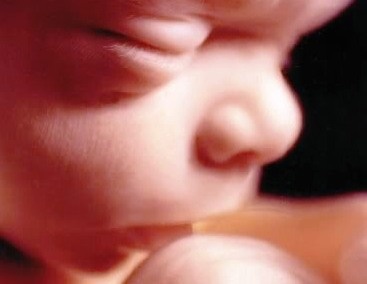

Principala evolutia a copilului fata de saptamana trecute este acumularea rapida de grasime.